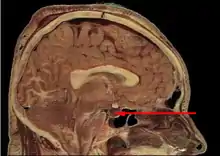

L'hypophyse se trouve dans une cavité osseuse, la fosse hypophysaire qui se situe dans l'os sphénoïde. Elle est protégée par la selle turcique. Elle est reliée à une autre partie du cerveau appelée l'hypothalamus par une tige hypophysaire (également appelée tige pituitaire). Elle produit des hormones qui gèrent une large gamme de fonctions corporelles, dont les hormones trophiques qui stimulent les autres glandes endocrines. Cette fonction lui a valu de se faire appeler par les scientifiques « glande maîtresse » du corps, mais aujourd'hui on sait que l'hypophyse est régulée par les hormones (neuro-hormones) émises par l'hypothalamus.

L'hypophyse est divisée en deux lobes : l'antéhypophyse (adénohypophyse) en avant, et la posthypophyse (neurohypophyse) en arrière. L'adénohypophyse dérive du plafond de la cavité buccale primitive (stomodeum), tandis que la neurohypophyse est une extension de l'hypothalamus, relié à celui-ci par la tige pituitaire, et contient les axones de neurones dont les corps cellulaires se trouvent dans l'hypothalamus. On peut également trouver entre l'antéhypophyse et la posthypophyse, une troisième structure, l'hypophyse intermédiaire, bien développée chez certaines espèces animales[Lesquelles ?] : chez l'humain, l'hypophyse intermédiaire (pars intermedia) est seulement visible en période fœtale et jusqu'à l'âge de dix ou vingt ans ; chez l'adulte, il subsiste quelques structures kystiques (follicules, restes de la poche de Rathke), ainsi qu'un infiltrat chromatophile basophile.